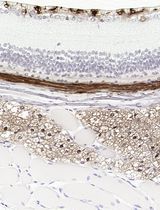

The major strength of this approach lies in its ability to reliably preserve both structural integrity and histological detail, which are essential for downstream applications such as H&E staining, immunohistochemistry, and immunofluorescence. Although the method involves steps that may appear harsh—such as drying and the addition of warm agarose—and FFPE processing can impose certain limitations, molecular analyses that are highly sensitive to fixation stress may be restricted. Nevertheless, this protocol effectively supports morphological assessment and protein-level studies. In our validation, we confirmed the expression of cancer diagnostic markers such as CK19, pan-CK, and P53 and further demonstrated that marker expression relevant to subtype classification could be evaluated using tissue proteomics–based analysis [9,19–21]. Overall, this protocol provides a practical and robust method for generating high-quality FFPE organoid slides, making it well-suited for cancer research, biomarker evaluation, and translational applications in personalized medicine.